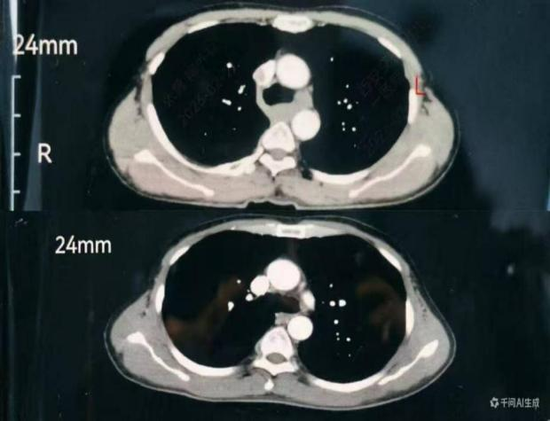

一是極致微創,創傷降至最低。摒棄傳統多切口模式,實現胸部無切口,僅在頸部、腹部各做3 - 5cm微小切口,借助高清腔鏡精準完成手術,減少組織損傷,減輕患者術后疼痛,降低并發癥風險。

此次成功開展“胸部無切口、頸腹3-5cm小切口、頸腹同步操作”的頸腹同步雙單孔微創食管癌根治術,是交大一附院胸外科在微創外科領域的重要突破,為食管疾病微創治療提供了可借鑒推廣的實踐路徑。